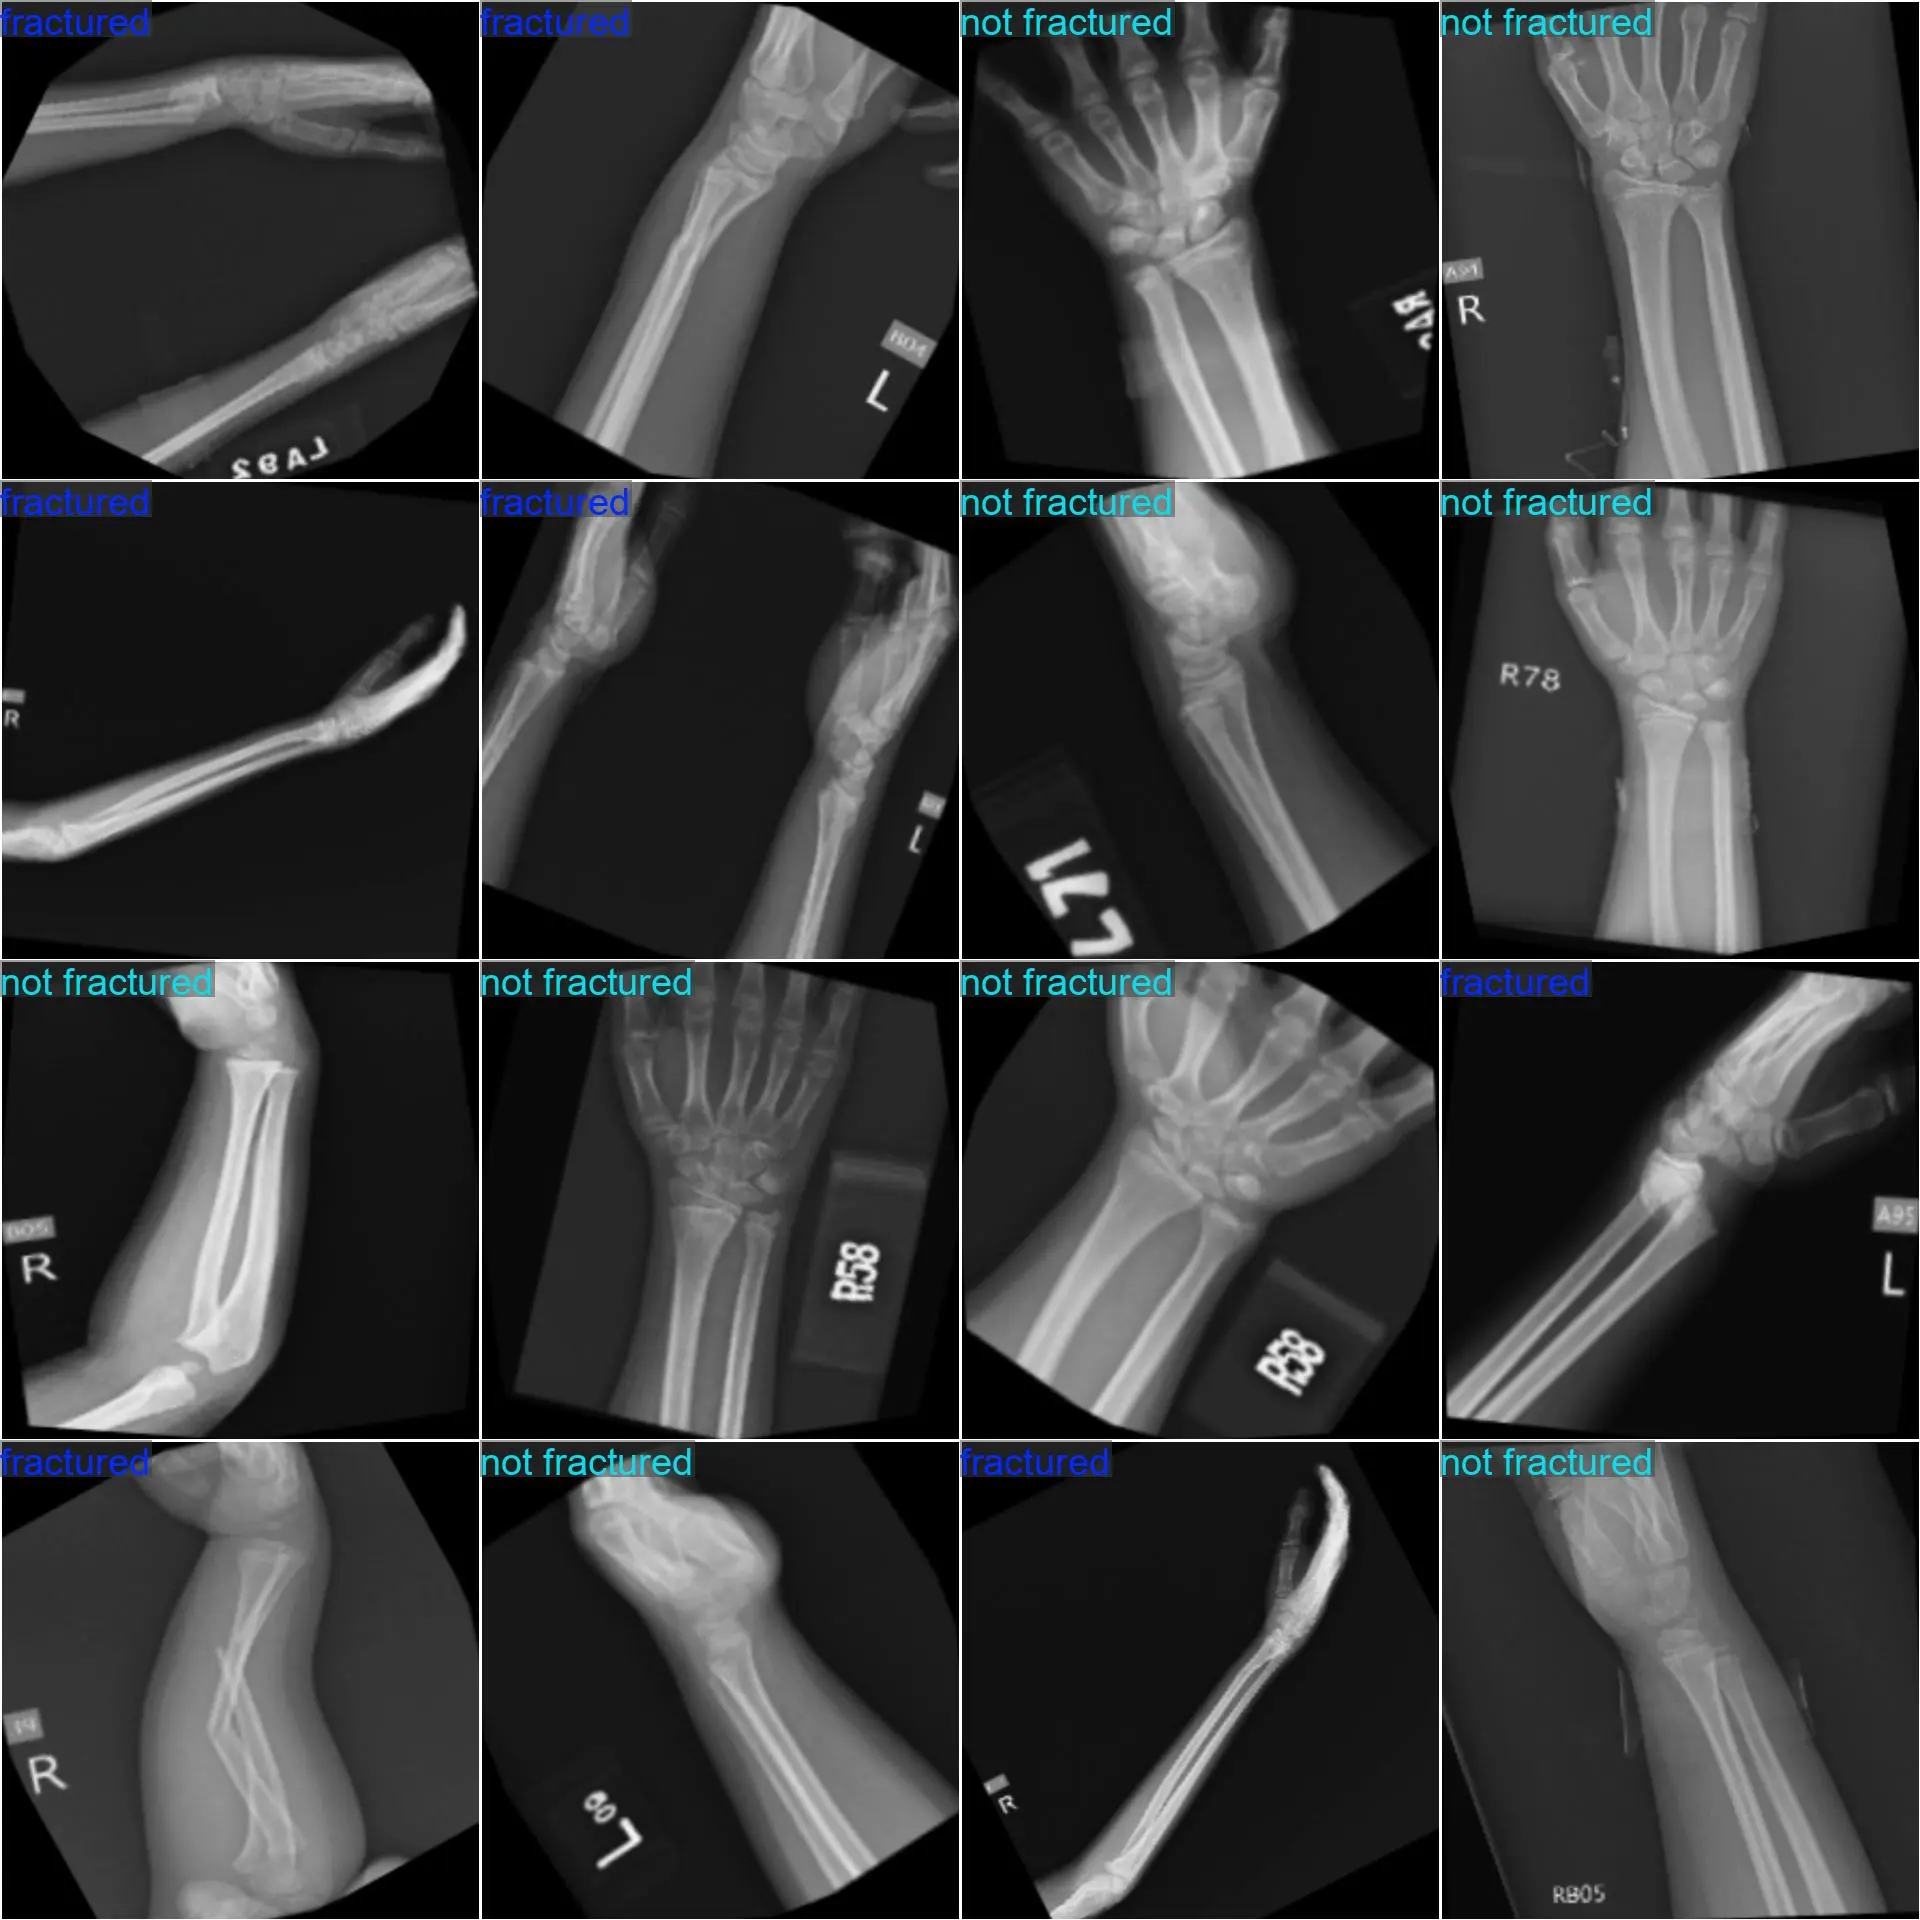

• 数据集介绍:医疗 X 光骨折检测分类数据集,真实采集医疗骨骼 X 光图片数据;

• 数据集类别:fractured、not fractured 两个类别;

• 标注说明:采用文件夹来区分不同的目标类别,标注质量高,可以直接用于如 YOLOCLS 的算法训练;